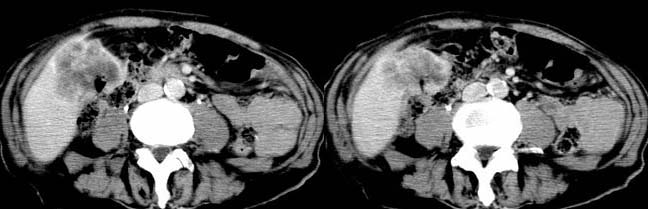

以下是引用余辉在2007-12-6 22:23:00的发言:[br]胆囊内多枚结石影,胆管全程扩张,右肝内病灶强化符合脓肿表现现(左肝病灶图像未传完),考虑急性梗阻性化脓性胆囊胆管炎合并肝多发脓肿(建议补传左肝病灶图像)